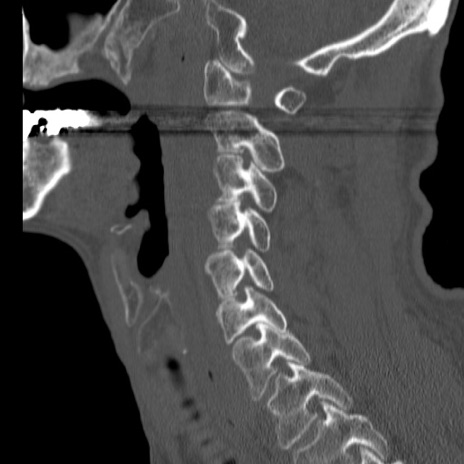

症例46 頚椎CT(矢状断像)

【症例】80歳代男性

【主訴】両側頚部〜上肢のしびれ

【現病歴】昨日、自宅内で転倒、その後より上記症状あり。意識障害なし。

【身体所見】両側上肢のallodynia(熱痛覚過敏)あり。MMTおよびDTRは正確な所見取れず。両上肢の挙上はなんとか可能。

異常所見と診断は?